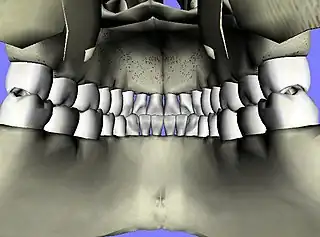

![]() Vista interna de la mandíbula | ||